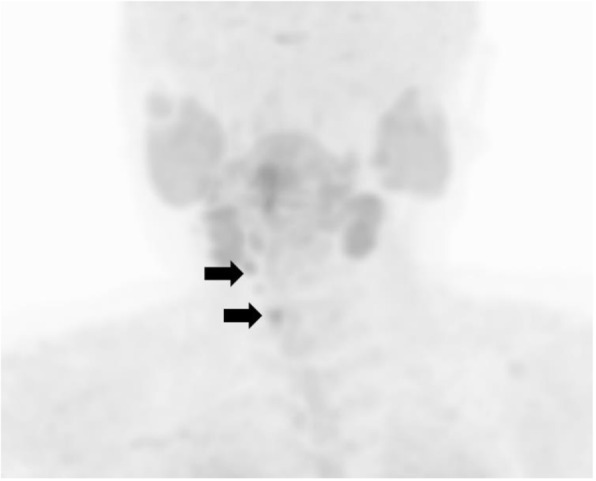

Fig. 7.

11C-methionine PET-CT findings after the removal of local recurrence. Methionine-positive tumors right next to the trachea (arrows)